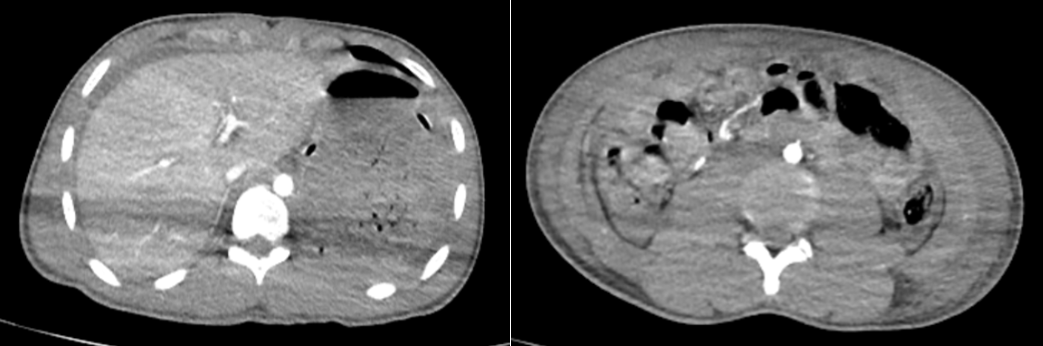

Ngày 12/01 bệnh nhân đau bụng dữ dội, bụng phản ứng, chụp chụp cắt lớp vi tính có hơi tự do ổ phúc mạc.

Hình ảnh hơi tự do ổ phúc mạc vào ngày thứ 12 sau nhập viện trên phim chụp cắt lớp vi tính